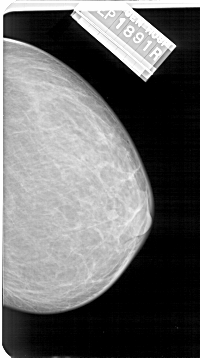

A_1568_1.RIGHT_MLO

RIGHT_MLO LINES 5356 PIXELS_PER_LINE 3346 BITS_PER_PIXEL 12 RESOLUTION 43.5 NON_OVERLAY